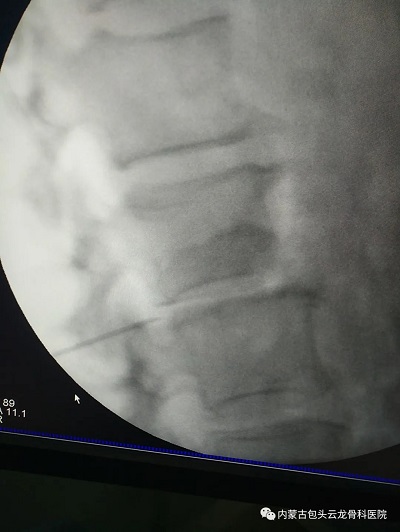

小杰和家人经过深思熟虑,决定接受这种治疗方式。治疗当天,小杰躺在了治疗床上,在C臂透视下,将针头精确地刺入病变神经根的周围,然后注入混合药物。整个过程并不痛苦,小杰感到腰部有些轻微的胀痛,但可以接受。

椎间孔硬膜外神经阻滞术手术影像